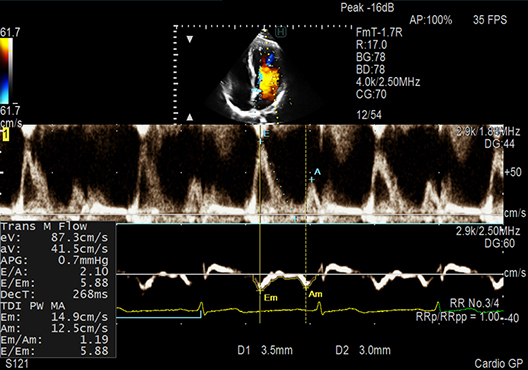

E/e', one of the key LV diastolic performance indices, is measured automatically in Dual Gate Doppler use. By using this in combination with R-R Navigation, iDGD detects an appropriate heartbeat automatically.

- Dual Gate Doppler: Enables observation of Doppler waveforms from two different locations in the same heart cycle.

- R-R Navigation: Enables the detection of a stable R-R interval automatically.